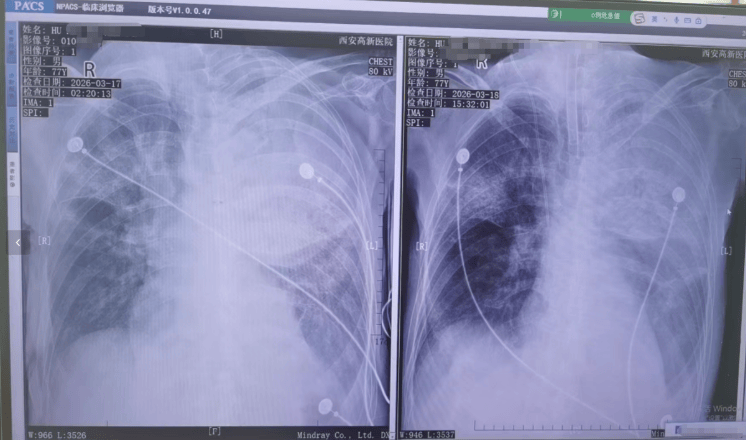

▲患者接受转院治疗

胡先生说,起初以为是感冒,住院治疗没有效果,还越来越严重,以至于病情危重,“整个肺部全白了”,并且出现呼吸衰竭,医院甚至下了病危通知书世界杯真钱开户 。3月17日,家人赶紧将父亲转院到西安高新医院抢救,到医院以后就住进了ICU。经检查,才发现是鹦鹉热衣原体感染导致的重症肺炎。胡先生提供的一份《西安高新医院诊断证明》显示,胡先生的父亲3月17日以重度肺炎入院。诊断为重症肺炎(鹦鹉热衣原体感染)I型呼吸衰竭,急性呼吸窘迫综合征,脓毒症等。

高和飞介绍,该病临床表现早期常表现为高热(39℃至40℃)、畏寒、头痛、肌肉酸痛、乏力等,类似流感或普通肺炎世界杯真钱开户 。呼吸系统症状以干咳、胸闷、呼吸困难为主,重症可迅速进展为肺炎、急性呼吸窘迫综合征(ARDS)。胡先生父亲病情之所以发展较快,主要与基层医院早期诊断困难、救治延迟,以及患者高龄、基础疾病、呼吸道吸入病原体量等因素有关。

▲患者胸片